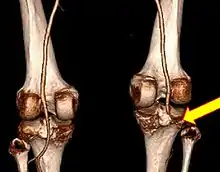

Plain X-rays, CT scan, ultrasonography, or MRI may help with the diagnosis.[2][10] Findings on X-ray that may be useful among those who have already reduced include a variable joint space, subluxation of the joint, or a Segond fracture.[5]

They may be divided into five types: anterior, posterior, lateral, medial, and rotatory.[4] This classification is based on the movement of the tibia with respect to the femur.[10] Anterior dislocations are the most common, followed by posterior dislocations.[2] They may also be classified based on what ligaments are damaged.[2]